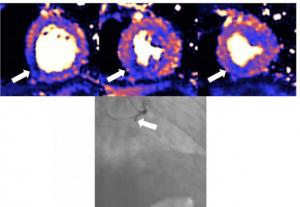

Around 50% of patients who have been hospitalised with severe COVID-19 and have raised levels of troponin have heart damage, according to a study published in the European Heart Journal. The injury was detected by magnetic resonance imaging (MRI) scans at least a month after discharge and includes myocarditis, infarction, ischaemia and combinations of all three.